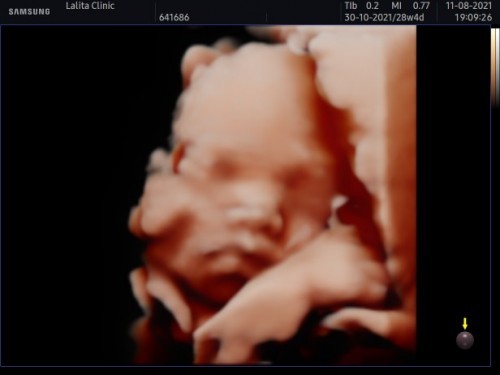

อัลตร้าซาวด์แบบนี้เสียเงินกี่บาทคะอยากลองไปซาวด์ดูคะ